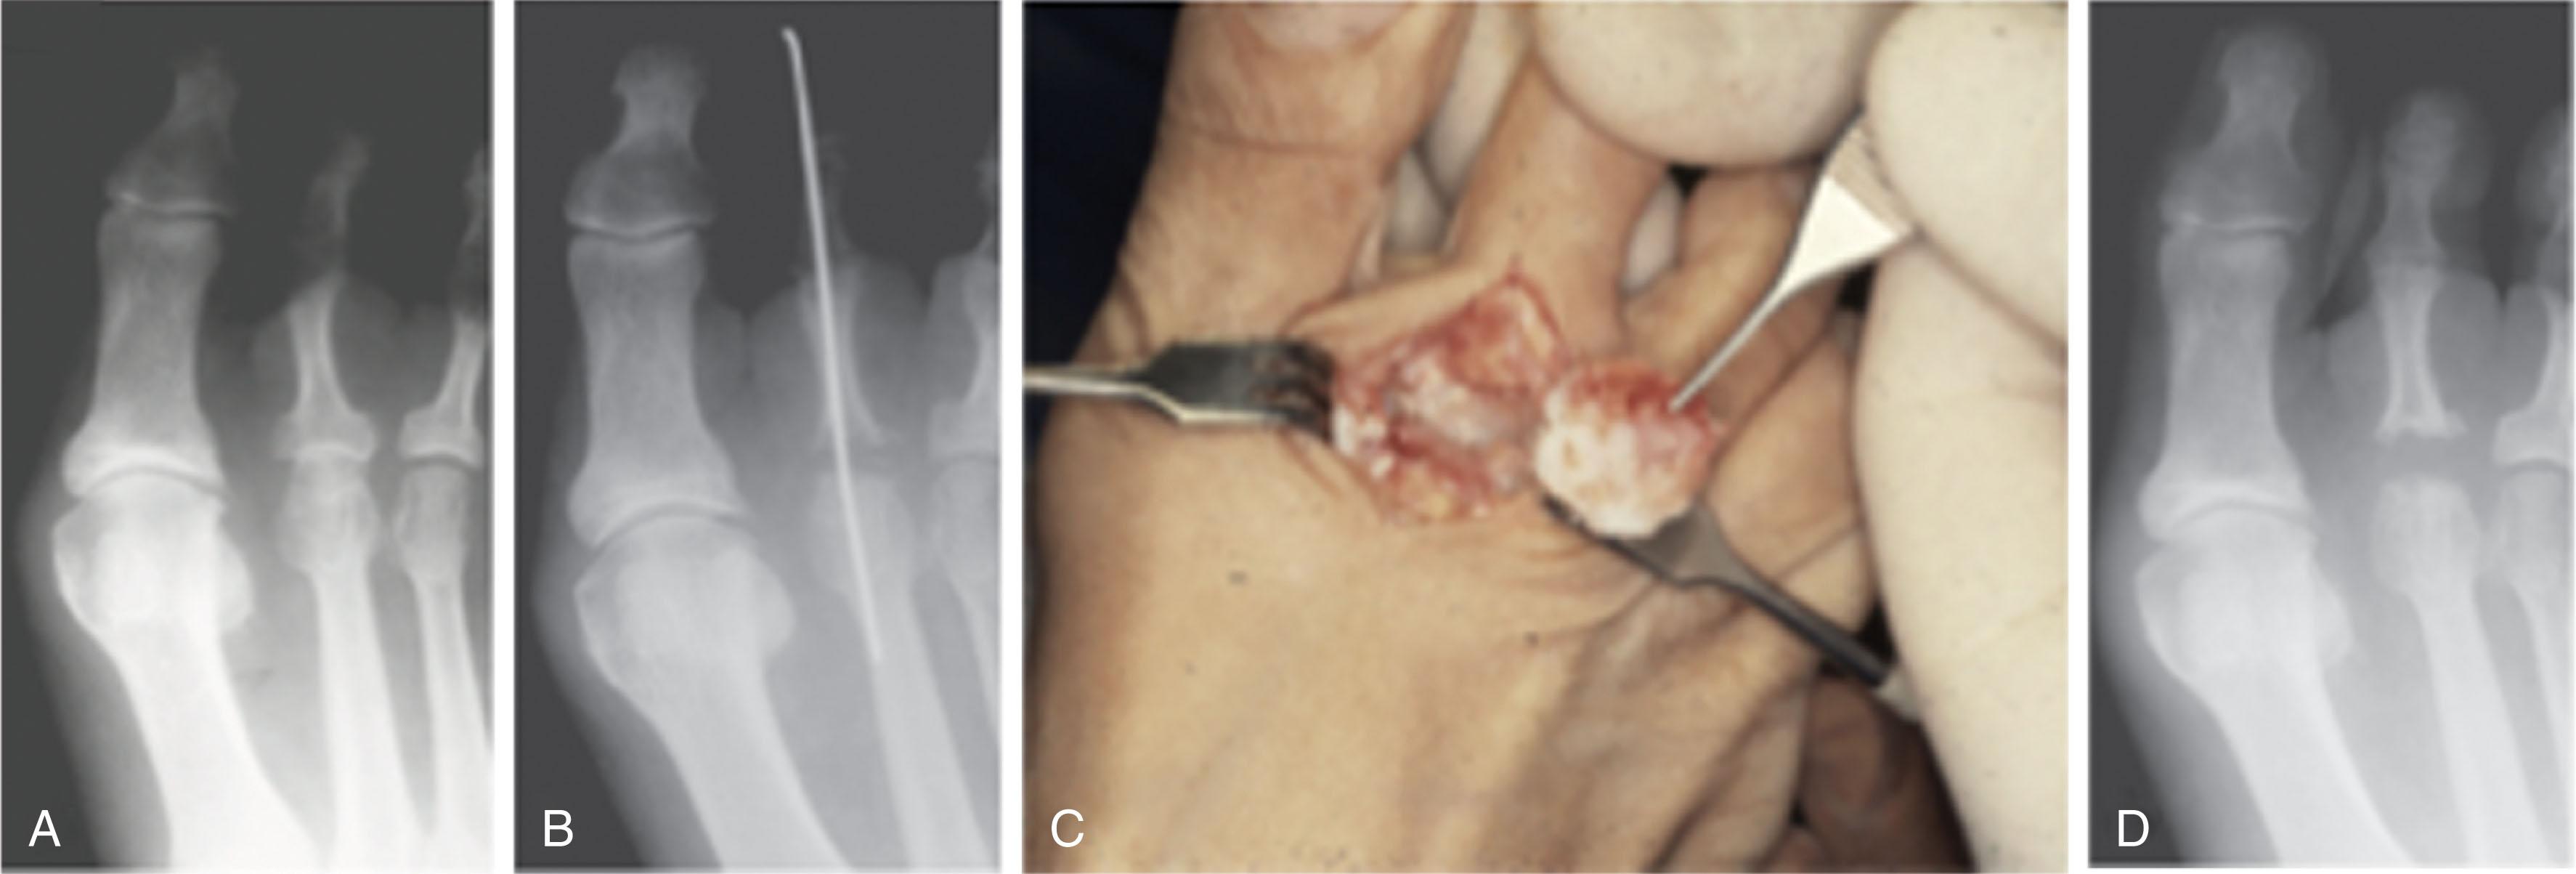

Intramedullary fixation for hammer toe correction has been advocated in an effort to secure permanent fixation without the use of Kirschner wires. Absorbable implants, screw fixation ( Figs. 9-41 and 9-42 ), wire loops, and other permanent intramedullary devices ( Fig. 9-43 ) have all been reported.

Fig. 9-41, Examples on intramedullary screws for hammer toe fixation. A , Placement of intramedullary Kirschner wire and cannulated screw from the tip of the toe. B , Cannulated screw fixation. C , Preoperative radiograph demonstrating subluxation of second and third metatarsophalangeal (MTP) joints and hammer toes of second and third toes. D , After intramedullary hammer toe fixation and distal osteotomies of second and third metatarsals. E , Intramedullary Herbert-type screws placed from the tips of the toes for treatment of hammer toe deformities. Note marked lesser MTP joint subluxation.

Fig. 9-42, Example of screw fixation with hammer toe repair. A , Clinical preoperative photograph and, B , radiograph of hammer toe deformities of second and third toes. C , Postoperative clinical photograph and, D , radiograph after placement of oblique proximal interphalangeal joint screw fixation.